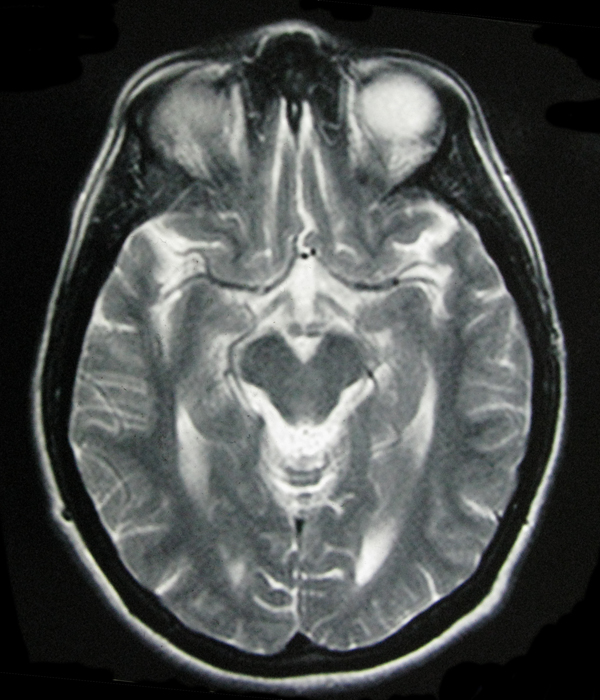

- My Brain in 2009